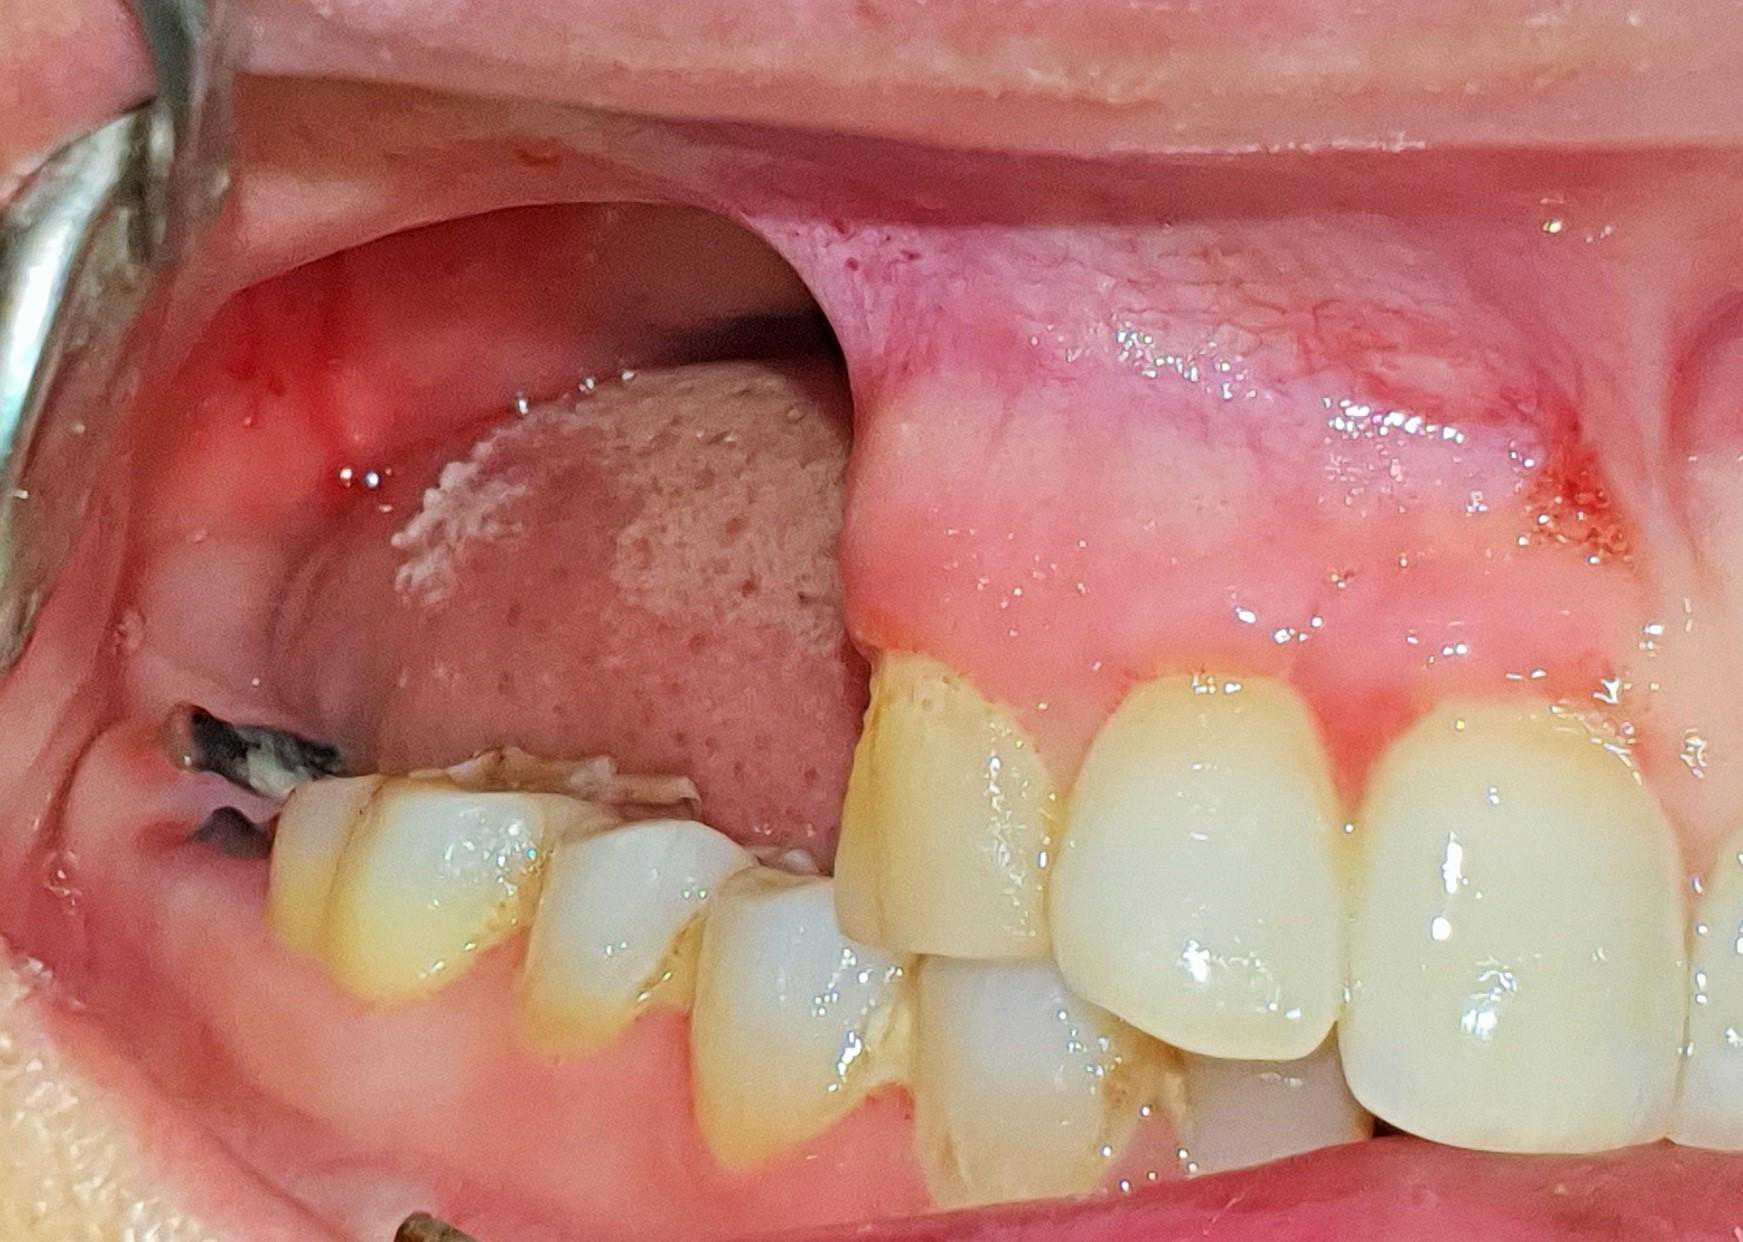

This is a case of Ameloblastic Fibro-Odontoma with a long term follow up.

https://demo.discussdentistry.com/forums/topic/post-mucormycosis-avascular-necrosis-of-maxilla-rehabilitation-with-zygomatic/#post-24499 <![CDATA[Post Mucormycosis Avascular necrosis of maxilla, rehabilitation with Zygomatic]]> https://demo.discussdentistry.com/forums/topic/post-mucormycosis-avascular-necrosis-of-maxilla-rehabilitation-with-zygomatic/#post-24499 Thu, 25 Aug 2022 12:14:40 +0000 Sankalp Mittal

• 20210604_101325 (2)20210604_101317 (2)20210604_103315 (2)20210604_102857 (2)20210604_104202 (2)20210604_104853 (2)20210824_105656 (2)20210824_112353 (2)20210824_114957 (2)20210824_131302 (2)20210826_100648 (2)20210826_100749 (2)20210826_100919 (2)20210914_183943 (2)20211001_17535220211012_18543620211012_192043 (2)20211012_185627 (2)20211012_195430 (3)20211027_193725 (2)20211027_200729 (2)20211027_200919